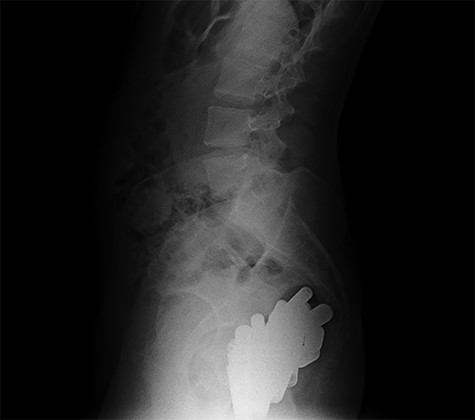

Erect abdominal X-rays (lateral view): confirmation of the presence of many radiopaque foreign bodies in the pelvis

At hospitalization, the clinical examination revealed moderate pain in the lower left part of the abdomen. Laboratory analyses demonstrated moderate neutrophilic leukocytosis. Abdominal X-rays revealed the presence of many radiopaque foreign bodies on the projection of the rectum, referable to stylus batteries (Figs 1 and 2).